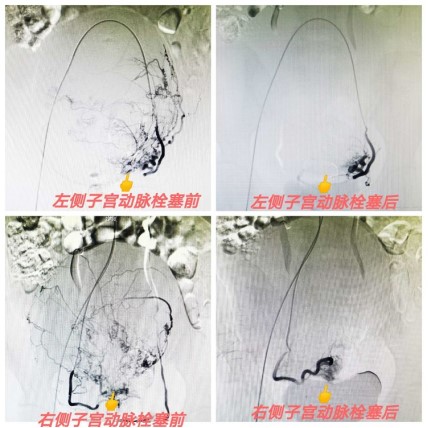

急診出血的介入治療

有效控制出血,降低死亡風(fēng)險(xiǎn),本技術(shù)省內(nèi)領(lǐng)先。